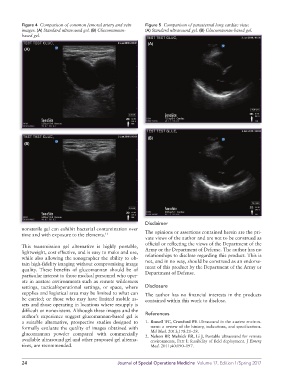

Figure 4 Comparison of common femoral artery and vein Figure 5 Comparison of parasternal long cardiac view.

images. (A) Standard ultrasound gel. (B) Glucomannan- (A) Standard ultrasound gel. (B) Glucomannan-based gel.

based gel.